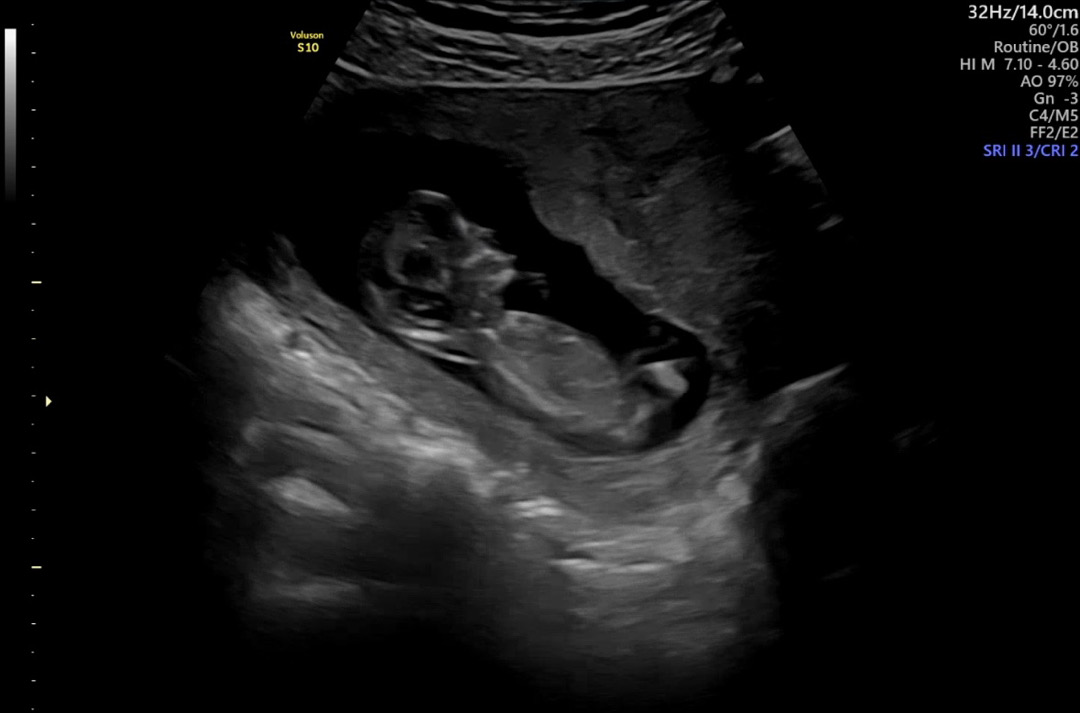

각도법 봐주세요!🩵

다른분들 사진, 댓글 봐도 전 각도법 아예 모르겠더라구요 ㅠㅠ 처음에는 어짜피 나중에 알게될텐데~했는데 12주 되니까 궁금해지는건 어쩔수가 없네요 8ㅅ8 고수님들 부탁드립니당 ㅎㅎ

이사진으론 알수가없어여